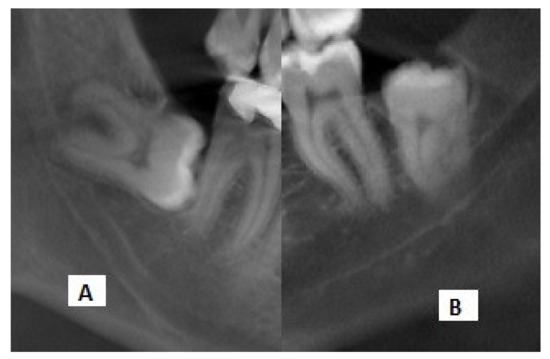

A total of 132 IMTMs with one of the risk factors of root darkening or interference with the white line of the MC on panoramic radiographs, according to the classification by Rood and Shehab, were evaluated. The radiographs were randomly selected by an experienced radiologist from the archives after applying the eligibility criteria. Information regarding the relationship of the IMTMs and the MC was recorded in a datasheet (Figure 2). Next, an experienced oral and maxillofacial radiologist, familiarized with CBCT interpretation, evaluated the cross-sectional, axial, and coronal views of the selected CBCT scans by Romexis software (R version 3.8.3, Planmeca, Helsinki, Finland) on a 19-inch monitor (Samsung, Seoul, Korea) in a semi-dark room.

Figure 2. Cropped panoramic radiographs showing the (A) interference with the white line and (B) darkening of roots.